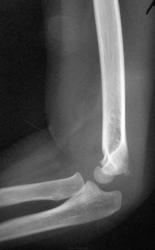

Пол пациента: Мужской пол Тип патологии: Травма Область исследования: Скелетно-мышечная система Методы исследования: Rg Травма. Пациент направлен на рентгенографию локтевого сустава https://radiomed.ru/sites/default/files/styles/case_slider_image/public/user/12/12.dscn0089a.jpg?itok=3NNM8UuI https://radiomed.ru/sites/default/files/styles/case_slider_image/public/user/12/13.dscn0090a.jpg?itok=sb-OhKYV https://radiomed.ru/sites/default/files/styles/case_slider_image/public/user/12/14.dscn0090ab.jpg?itok=Q4D_a_r1 ID:23259 Чт, 20/09/2012 - 21:19 #1 Сан Саныч1 Не на сайте Был на сайте: 11 месяцев 4 недели назад Зарегистрирован: 07.06.2010 - 21:17 Публикации: 2114 Вывих локтевой с эпифизеолизом локтевой и лучевой? Хочешь сделать что-то нормально - сделай это сам! Чт, 20/09/2012 - 23:16 #2 И.Бондаренко Не на сайте Был на сайте: 2 дня 6 минут назад Зарегистрирован: 13.09.2011 - 22:55 Публикации: 9206 Не работаю с детьми, поэтому вопрос: почему вывих локтевой? Вроде всё на месте. Эпифизеолиз согласен, только лучевой. Пт, 21/09/2012 - 14:50 #3 pronto Не на сайте Был на сайте: 1 год 2 месяцев назад Зарегистрирован: 22.02.2011 - 18:50 Публикации: 114 норма Пт, 21/09/2012 - 17:39 #4 Соломин Виталий... Не на сайте Был на сайте: 6 лет 7 часов назад Зарегистрирован: 04.04.2012 - 21:47 Публикации: 1096 pronto wrote: норма Почему-то при увеличении у меня снимки синие, ничего не понять. А если смотреть маленькие изображения (хотя может там чего-то не так разглядел) на возрастную норму похоже у маленького ребенка. Сб, 22/09/2012 - 10:02 #5 Dr.Yllich Не на сайте Был на сайте: 1 год 4 месяцев назад Зарегистрирован: 01.05.2011 - 22:52 Публикации: 1196 Остео-эпифизеолиз плеча (головчатого возвышения) без смещенияПриложения: С уважением. Ильич. Сб, 22/09/2012 - 10:08 #6 olle Не на сайте Был на сайте: 9 лет 9 месяцев назад Зарегистрирован: 07.10.2011 - 21:25 Публикации: 136 Мне кажется Dr.Yllich прав Сб, 22/09/2012 - 13:52 #7 Dr.Yllich Не на сайте Был на сайте: 1 год 4 месяцев назад Зарегистрирован: 01.05.2011 - 22:52 Публикации: 1196 Поддержка красивой девушки окрыляет. Спасибо! Ильич. С уважением. Ильич. Сб, 22/09/2012 - 13:56 #8 Катенёв Валенти... Не на сайте Был на сайте: 7 лет 1 месяц назад Зарегистрирован: 22.03.2008 - 22:15 Публикации: 54876 olle wrote: Мне кажется Dr.Yllich прав Мне тоже. Сб, 22/09/2012 - 20:08 #9 olle Не на сайте Был на сайте: 9 лет 9 месяцев назад Зарегистрирован: 07.10.2011 - 21:25 Публикации: 136 Пасибки, Yllich, я польщена... Сб, 22/09/2012 - 21:57 #10 Соломин Виталий... Не на сайте Был на сайте: 6 лет 7 часов назад Зарегистрирован: 04.04.2012 - 21:47 Публикации: 1096 Dr.Yllich wrote: Остео-эпифизеолиз плеча (головчатого возвышения) без смещения Рассмотрел «поближе». Похоже, все-таки ошибся, перелом плеча есть.

Вывих локтевой с эпифизеолизом локтевой и лучевой?

Не работаю с детьми, поэтому вопрос: почему вывих локтевой? Вроде всё на месте. Эпифизеолиз согласен, только лучевой.

Остео-эпифизеолиз плеча (головчатого возвышения) без смещения

Рассмотрел «поближе». Похоже, все-таки ошибся, перелом плеча есть.